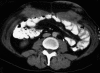

Malignant mesothelioma is a highly aggressive neoplasm. The incidence of malignant mesothelioma is increasing worldwide. Diffuse malignant peritoneal mesothelioma (DMPM) represents one-fourth of all mesotheliomas. Association of asbestos exposure with DMPM has been observed, especially in males. The great majority of patients present with abdominal pain and distension, caused by accumulation of tumors and ascitic fluid. In the past, DMPM was considered a pre-terminal condition; therefore attracted little attention. Patients invariably died from their disease within a year. Recently, several prospective trials have demonstrated a median survival of 40 to 90 mo and 5-year survival of 30% to 60% after combined treatment using cytoreductive surgery and perioperative intraperitoneal chemotherapy. This remarkable improvement in survival has prompted new search into the medical science related to DMPM, a disease previously ignored as uninteresting. This review article focuses on the key advances in the epidemiology, diagnosis, staging, treatments and prognosis of DMPM that have occurred in the past decade.